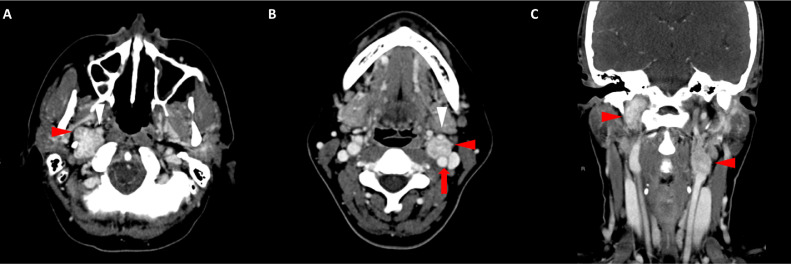

胸部、腹部和骨盆的對比增強(qiáng)動脈和靜脈期 CT 顯示多個(gè)圓形、主要是血管豐富的異質(zhì)腫塊,具有囊性和實(shí)性成分,起源于胃底和胃體(圖 2-4)。 病變部分呈外生結(jié)構(gòu),被認(rèn)為位于粘膜下層。 在頸部多發(fā)同步性副神經(jīng)節(jié)瘤的情況下,賊初的鑒別診斷包括多發(fā)性副神經(jīng)節(jié)瘤、多發(fā)性 GIST 以及轉(zhuǎn)移性疾病。

Fig. 2

圖 2:多發(fā)胃腸道間質(zhì)瘤的軸位 CT 圖像。 (A 和 B)軸位動脈相增強(qiáng) CT 圖像和(C 和 D)軸位靜脈相增強(qiáng) CT 圖像顯示多個(gè)圓形、不均勻、增強(qiáng)的腫塊,具有實(shí)性和囊性成分。 腫塊位于粘膜下,結(jié)構(gòu)呈外生。